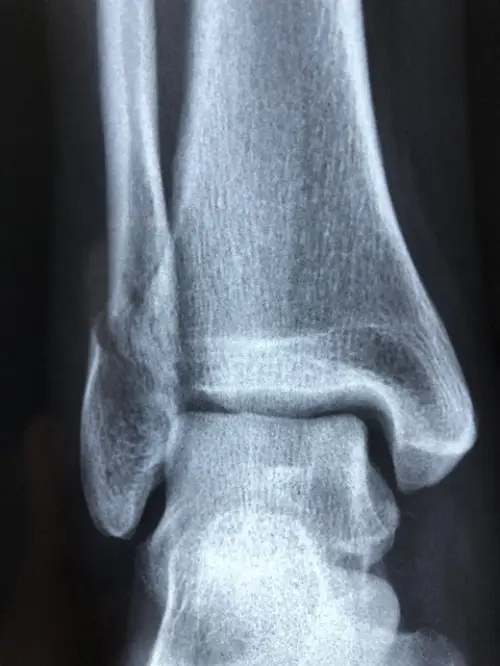

발목을 접질릴 때 뚝 하는 소리가 들렸다면 인대가 심하게 손상되었거나 골절이 동반될 가능성이 높습니다. 이 또한 병원에서 정확한 영상 검사와 치료를 받아야 안전합니다.

상기 증상들이 나타났을 때는 X-ray, MRI 등 영상 검사를 통해 인대 파열 정도, 골절 여부, 주변 조직 손상 등을 정확히 확인하는 것이 중요합니다. 이를 통해 적절한 치료계획을 세울 수 있습니다.